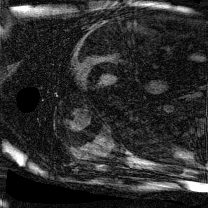

Supervised Deep-Learning (DL)-based reconstruction algorithms have shown state-of-the-art results for highly-undersampled dynamic Magnetic Resonance Imaging (MRI) reconstruction. However, the requirement of excessive high-quality ground-truth data hinders their applications due to the generalization problem. Recently, Implicit Neural Representation (INR) has appeared as a powerful DL-based tool for solving the inverse problem by characterizing the attributes of a signal as a continuous function of corresponding coordinates in an unsupervised manner. In this work, we proposed an INR-based method to improve dynamic MRI reconstruction from highly undersampled k-space data, which only takes spatiotemporal coordinates as inputs. Specifically, the proposed INR represents the dynamic MRI images as an implicit function and encodes them into neural networks. The weights of the network are learned from sparsely-acquired (k, t)-space data itself only, without external training datasets or prior images. Benefiting from the strong implicit continuity regularization of INR together with explicit regularization for low-rankness and sparsity, our proposed method outperforms the compared scan-specific methods at various acceleration factors. E.g., experiments on retrospective cardiac cine datasets show an improvement of 5.5 ~ 7.1 dB in PSNR for extremely high accelerations (up to 41.6-fold). The high-quality and inner continuity of the images provided by INR has great potential to further improve the spatiotemporal resolution of dynamic MRI, without the need of any training data.

翻译:在这项工作中,我们建议了一种基于IRI的方法,用这种方法来改进动态磁共振感应成像(MRI)重建,而该方法只是以高度低劣的 k-空间数据为基础,而该数据仅以磁共振坐标作为投入。具体地说,拟议的IRI将动态MRI图像作为一种隐含功能来表示,并将其编码到神经网络中。网络的权重仅从稀有的(k, t)空间数据本身中学习,而没有外部培训数据集或先前的图像。 利用基于IRI的强有力隐含性稳定化,同时不以清晰的动态和时空坐标坐标坐标坐标坐标作为投入。 拟议的IRIR将动态MRI图像作为一种隐含功能,将其编码到神经网络中。网络的权重仅从淡化的(k, t)空间数据本身学习,而没有外部培训数据集或先前的图像。